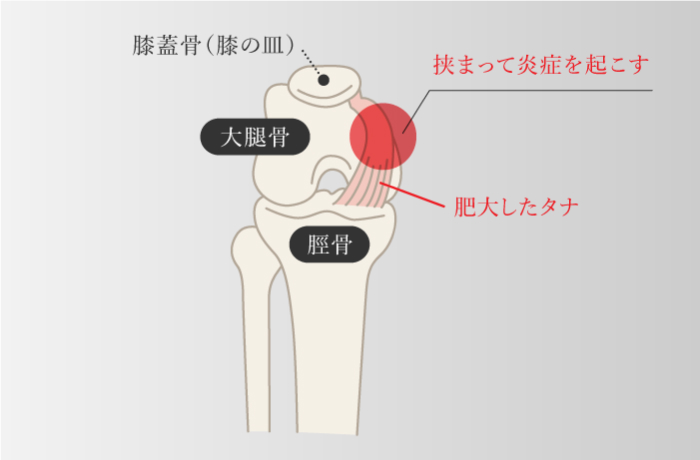

滑膜病変・棚障害

-

膝の曲げ伸ばしを繰り返すことで、膝関節内側にあるタナ(滑膜ヒダ)が膝の皿と大腿骨の間に挟まり、大腿骨の下端の膨らんだ部分とこすれて炎症を起こして、腫れや痛みが出るもの。膝関節に可動域制限やひっかかり感、クリック音などがでることがある。